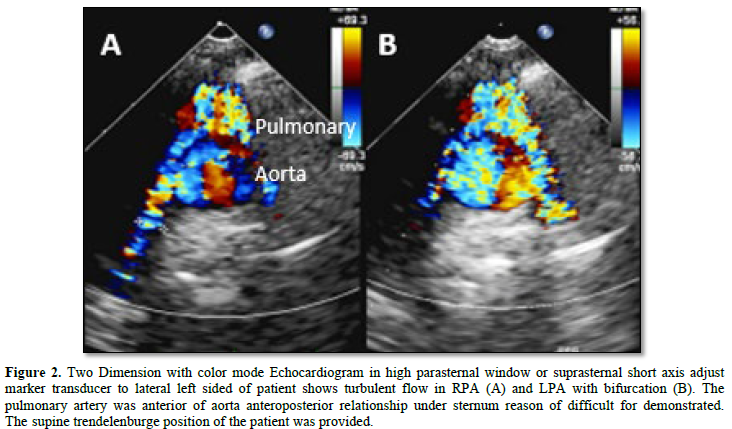

PA branches size and anatomy: The American society of echocardiography was recommended in post-operative TGA use standard view comprehensive echocardiography imaging. Especially, the suprasternal short axis or high parasternal view had the benefit of demonstrating the anatomy and anterior relationship of the branch pulmonary arteries to the aorta after the LeCompte maneuver. Because of the PA branches was straddling the aorta difference normal anatomy pattern (Figures 1 & 2). In addition to size, pressure gradient is also important for evaluation. Although McGoon ratio had a benefit in tetralogy of Fallot and other congenital heart disease of describing abnormal size pulmonary artery. The McGoon ratio able to apply to assessment PA size compares with abdominal descending aorta (DAo) from equation McGoon ratio = RPA+LPA/DAo. (Normal > 1.8) [13]. The Z score of pulmonary artery size was popular in CT or the MRI. But several cases in TGA after repair by LeCompte maneuver procedure, the PA branches will stretch and slightly undersize,if we compare with the pulmonary artery Z-score from normal population group may be extremely under the size of the body surface area, this limitation of interpretation must be concerned. (Normal range of Z score -2 to 2).